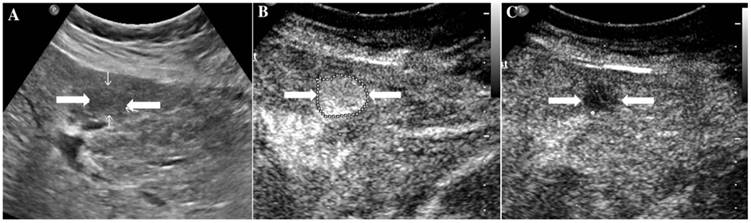

At last, of the 37 observations classified as LR-5, 33 (89.19%) were pathologically confirmed as malignant including 1 ICC (2.7%) and 32 HCC (86.49%). The typical ultrasound images are shown in Figure 1. However, 4 lesions (10.81 %) were histologically proved to be benign, 3 regenerative nodule (8.11%) (Figure 2) and 1 focal nodular hyperplasia (2.7%). With respect to the 8 LR-4 observations, 4 cases (50%) turned out to be HCCs (Figure 3). Angioma, focal nodular hyperplasia (Figure 4) and regenerative nodule accounts for 12.5% (1/8), 12.5% (1/8) and 25% (2/8) respectively. Nine observations categorized as LR-M consist of 7 (77.78%) HCC (Figure 5), 1 (11.11%) ICC and 1 (11.11%) RLH, based on pathological findings. The correct diagnoses of HCC, ICC and benign lesions were used to measure diagnostic accuracy for LI-RADS-CEUS. An example of successful categorization of HCC as LR-3 was shown in Figure 6. For the diagnosis of HCC, the overall diagnostic accuracy of LR-5 was 86.49 % (32/37) and that of LR-4 was 50% (4/8). However, the diagnostic accuracy of LR-M was only 11.11% in the retrospective study (Table 3).

Figure 5

It illustrates an example of misinterpretation with LI-RADS-CEUS (LR-M). The ultimate pathological diagnosis was HCC. A. Conventional B-mode image showed a 2.0cm hypoechoic nodule (arrows) on the right hepatic lobe of a 55-year-old male. B. CEUS showed hyperenhancement (arrows) during the arterial phase. C. The washout started after 50 seconds. D. CEUS showed obvious hypoenhancement (arrows) during the late phase.

Figure 6

The assigned LI-RADS category of this patient was LR-3. Hepatocellular carcinoma (HCC) was confirmed by histopathology. A. Conventional B-mode ultrasound showed a hyperechoic nodule (arrows) of about 1.6cm on the right hepatic lobe of a 36-year-old male patient. CEUS displayed hypoenhancement (arrows) in the arterial phase (Fig. 6B), portal phase (Fig. 6C) and late phase (Fig. 6D).